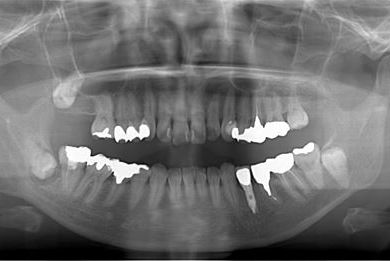

| 性別/年齢 | 女性 / 54歳 | ||||||||||||||||||||||||||||||||

| 主訴 | 下顎の奥歯を抜歯したままになっており、歯茎が少しやせて、両側の歯が少し倒れているような気がする。可能であればインプラントを入れたい。 | ||||||||||||||||||||||||||||||||

| 治療内容 | インプラント1本、メタルボンドセラミック1本 | ||||||||||||||||||||||||||||||||

| 総治療費 | 445,238円 | ||||||||||||||||||||||||||||||||

| 治療期間 | 5ヶ月 |